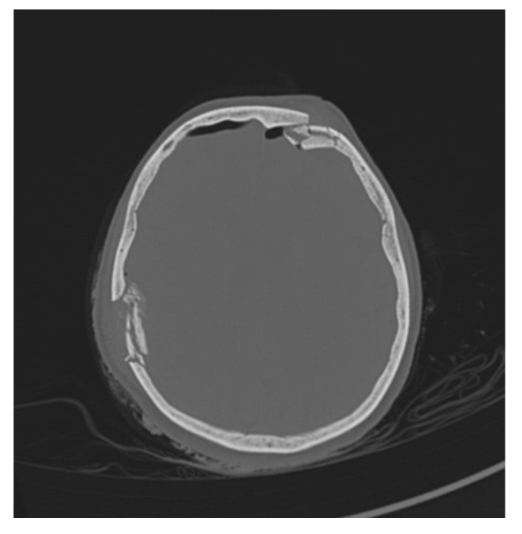

<p>What is the pathology?</p>

What is the pathology?

Skull fracture along lambdoid suture line.

Sits along the suture and the regular suture pattern is abnormal.

Best seen on non-contrast brain bone window.